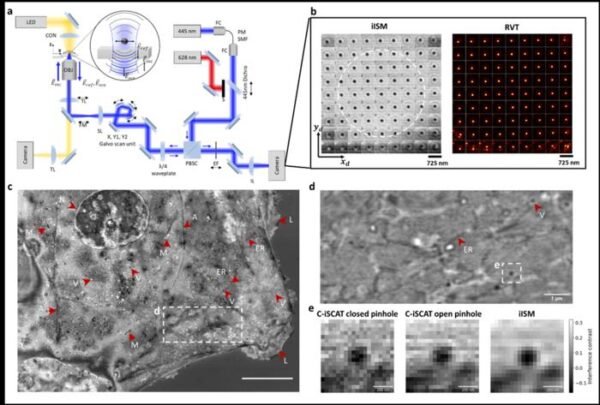

Stanfordo inžinieriai sukūrė iISM mikroskopą, kuris leidžia stebėti gyvas ląsteles be fluorescencinių žymių, pasiekdamas 120 nanometrų raišką.